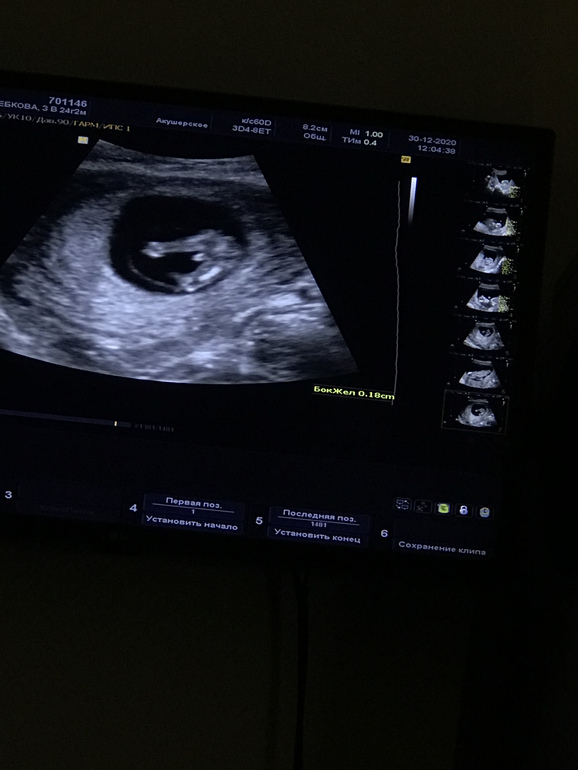

1 скрининг прошёл)

Та, которая больше всех зарекалась не верить полу на первом скрининге, сдаётся и закрашивает кружок) У нас будет ещё один мальчик! Сыночек, братик 😭😭😭 Так рада, что страшно поверить)

Все хорошо, ктр 66 мм, пдр на 10.07.21 нарисовался. Очень долго не показывал носовую кость, всячески уворачивался, пришлось ходить, потом и трансвагинально смотрели. Слава Богу нашли 🙏🏼 ТВП 1,7 мм. Егоза, стоял на голове почти все узи ) и ручки к лицу тянул)

Ни разу не пожалела, что не попала на узи от ЖК и пошла платно. Не зря ЦИР так хвалят